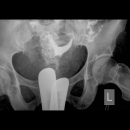

HSG